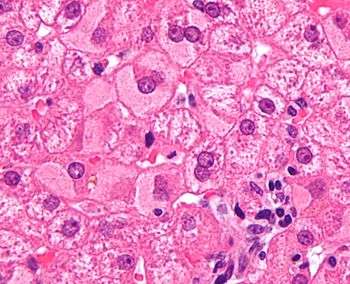

- Fatty liver disease (hepatic steatosis) is a reversible condition where large vacuoles of triglyceride fat accumulate in liver cells.[6] Non-alcoholic fatty liver disease is a spectrum of disease associated with obesity and metabolic syndrome.[7]